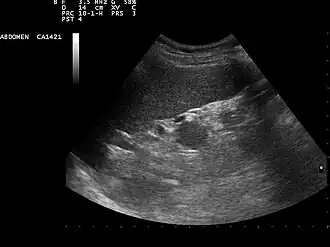

Sistema digestivo

En la ecografía abdominal, se forman imágenes de los órganos sólidos del abdomen como el páncreas, la aorta, la vena cava inferior, el hígado, la vesícula biliar, los conductos biliares, los riñones y el bazo. Las ondas sonoras son bloqueadas por el gas en el intestino y atenuadas en diferentes grados de grasa, por lo que hay capacidades de diagnóstico limitadas en esta área. El apéndice a veces se puede ver cuando se inflama.[20]